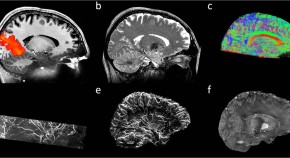

In order to test whether there is a cortical depth compartmentalization in the processing of external and internally-generated visual contents, Iamshchinina et al use high-resolution fMRI at 7 T in participants performing a mental rotation task. They demonstrate that feedforward and feedback representations during mental rotation manifest at differentiable grey matter depth in early visual cortex, thereby reflecting a general strategy for implementing multiple cognitive functions within a single brain region.